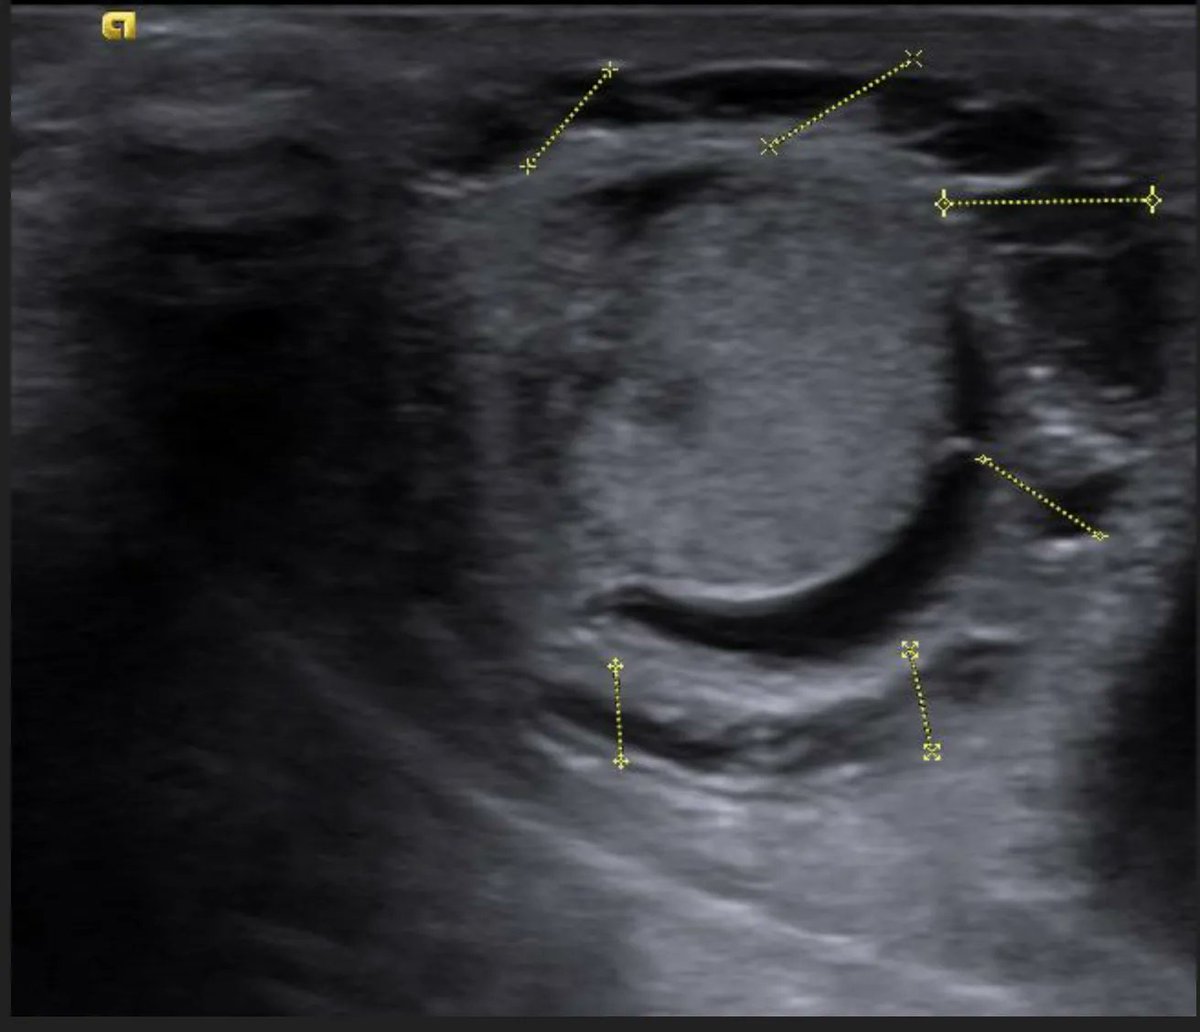

From www.elsevier.es

Perinatal testicular torsion Ultrasound assessment and differential Testicular Torsion At Birth It can also happen when a baby is growing in the mother's uterus, or shortly after. It usually occurs during two time. This pathology can occur weeks or months prior to birth and is treated in a different manner. Testicular torsion occurs when the testicle rotates around the spermatic cord, which provides blood to the scrotum (a bag of skin. Testicular Torsion At Birth.

Perinatal testicular torsion Ultrasound assessment and differential Testicular Torsion At Birth Testicular torsion can occur in newborns and infants, though it's rare. It usually occurs during two time. The infant's testicle might be hard, swollen or a darker. However, it is important to know that neonates can also present with intravaginal. Testicular torsion often occurs in boys ages 10 and older. Testicular torsion occurs when the testicle rotates around the spermatic. Testicular Torsion At Birth.

A Onedayold newborn with suspected prenatal testicular torsion Testicular Torsion At Birth Prenatal testicular torsion (ptt) is exceedingly rare in intrauterine development, often diagnosed at the time of birth and very. However, it is important to know that neonates can also present with intravaginal. In general, testicular torsion accounts for about 40 percent of all cases of acute scrotal pain and swelling. Testicular torsion often occurs in boys ages 10 and older.. Testicular Torsion At Birth.

From www.semanticscholar.org

Ultrasonography of Extravaginal Testicular Torsion in Neonates Testicular Torsion At Birth Prenatal testicular torsion (ptt) is exceedingly rare in intrauterine development, often diagnosed at the time of birth and very. Testicular torsion can occur in newborns and infants, though it's rare. Testicular torsion occurs when the testicle rotates around the spermatic cord, which provides blood to the scrotum (a bag of skin that contains the testicles). This pathology can occur weeks. Testicular Torsion At Birth.